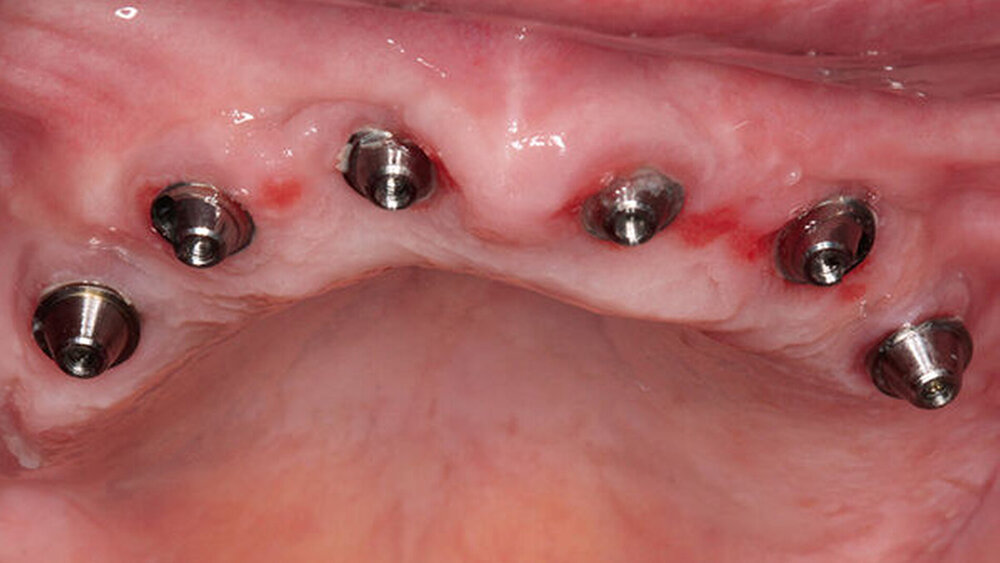

Buhtz: Korrekt, die Voraussetzung ist lediglich die Generierung von DICOM- und STL-Daten, die im Computer exakt übereinandergelegt werden können. Dann erfolgen die Behandlungsplanung wie gewohnt mit ICX-Magellan und die provisorische ‧Versorgung mit dem präfabizierten, chairside hergestellten verklebten PMMA-Provisorium (ICX-‧Smile‧bridge). Seit eineinhalb Jahren arbeiten wir zudem mit dem medentis Fräszentrum Denta5 zusammen.

Buhtz: Wir schicken die Scan-Daten, ein Wax-up und ggf. das Modell mit den Laborimplantaten an das medentis-Fräszentrum und erhalten zwei Tage später die verschraubte Unterkonstruktion. Denta 5 gibt es bereits seit einigen Jahren. Doch erst seit wir einen eigenen Modellscanner haben, stellen wir verschraubte Brücken auf diese Weise her. Jetzt habe ich eine Zahntechnikerin, die damit gut klarkommt. Full-arch-Versorgungen sind bei uns allerdings nicht das Tagesgeschäft, wir machen das vielleicht zehn- bis zwanzigmal pro Jahr. Unsere Patientenklientel ist in der Regel nicht zahnlos.